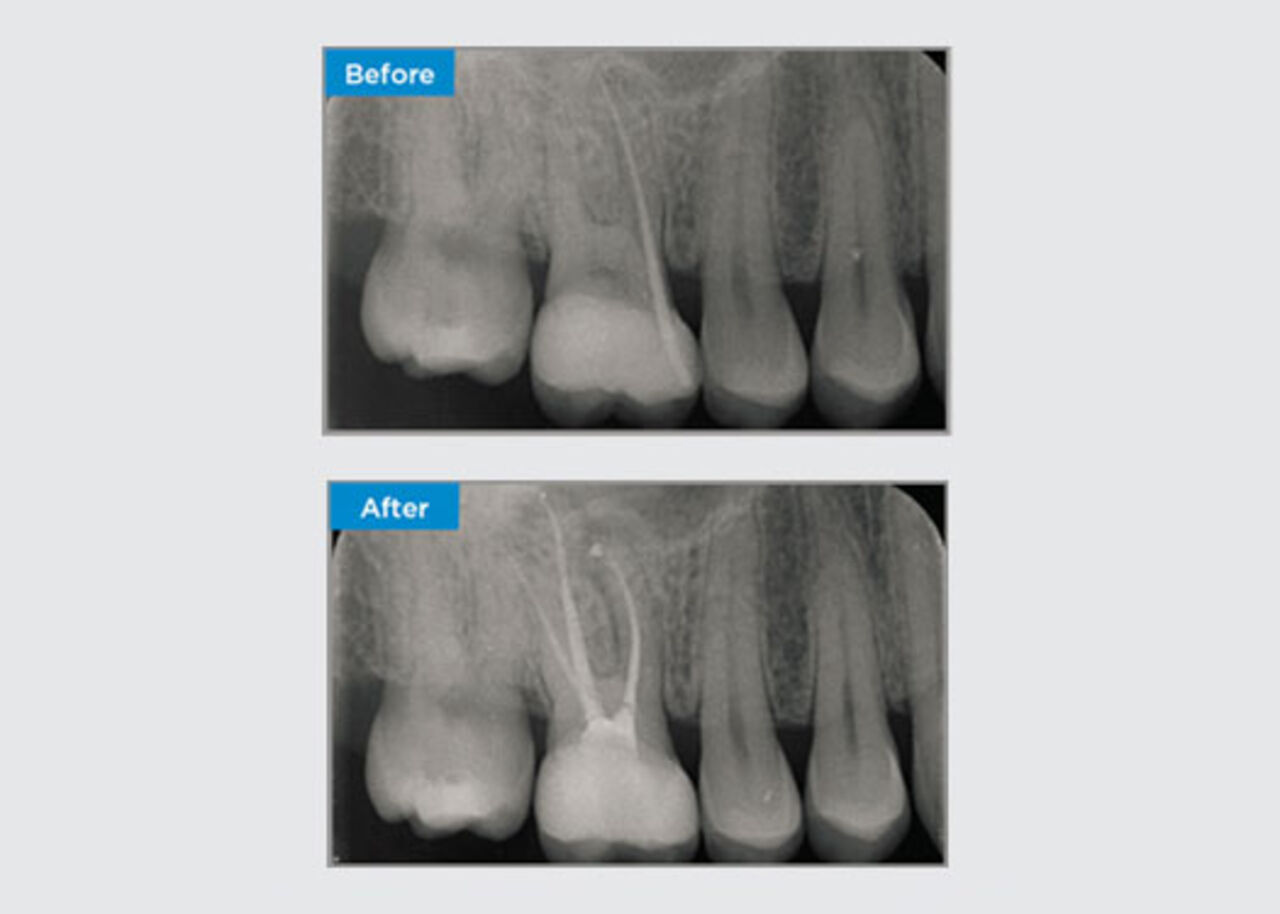

A 35 year old female patient presented after referral from a Specialist Periodontist. During the initial endodontic assessment the patient mentioned crown lengthening had been performed, prior to placement of the crown on tooth 16, two years earlier. Two months prior to the patient presenting, she had noted swelling of the palatal gingiva. The patient’s general dental practitioner had discovered a 7mm periodontal pocket adjacent the palatal sinus tract associated with tooth 16. The patient was referrred to a Specialist Periodontist. The Specialist Periodontist diagnosed a primary endodontic - secondary periodontal lesion. The patient had satisfactory oral hygiene and was a regular dental attender. Tooth 16 was tender to percussion. It was noted that the crown margins were satisfactory and the periodontal pockets around tooth 16 were less than 2mm deep on the buccal aspect, however on the palatal surface, adjacent the sinus tract there was a 6.5mm isolated periodontal pocket. Thermal testing of tooth 16 revealed a negative response. Tooth 16 had risk factors for apical periodontitis such as: a negative response to thermal testing, tenderness to percussion, a history of a deep restoration following crown lengthening surgery and radiographically identifiable periapical disease. Tooth 16 did not have a history of pain on biting or chewing, which may indicate a crack communicating with the pulp and/or periodontal tissues. The patient had no risk factors for periodontal disease and there was no abnormally deep pocketing present around any other teeth.

Dr Omar Ikram, Endodontist, Crows Nest, NSW Australia